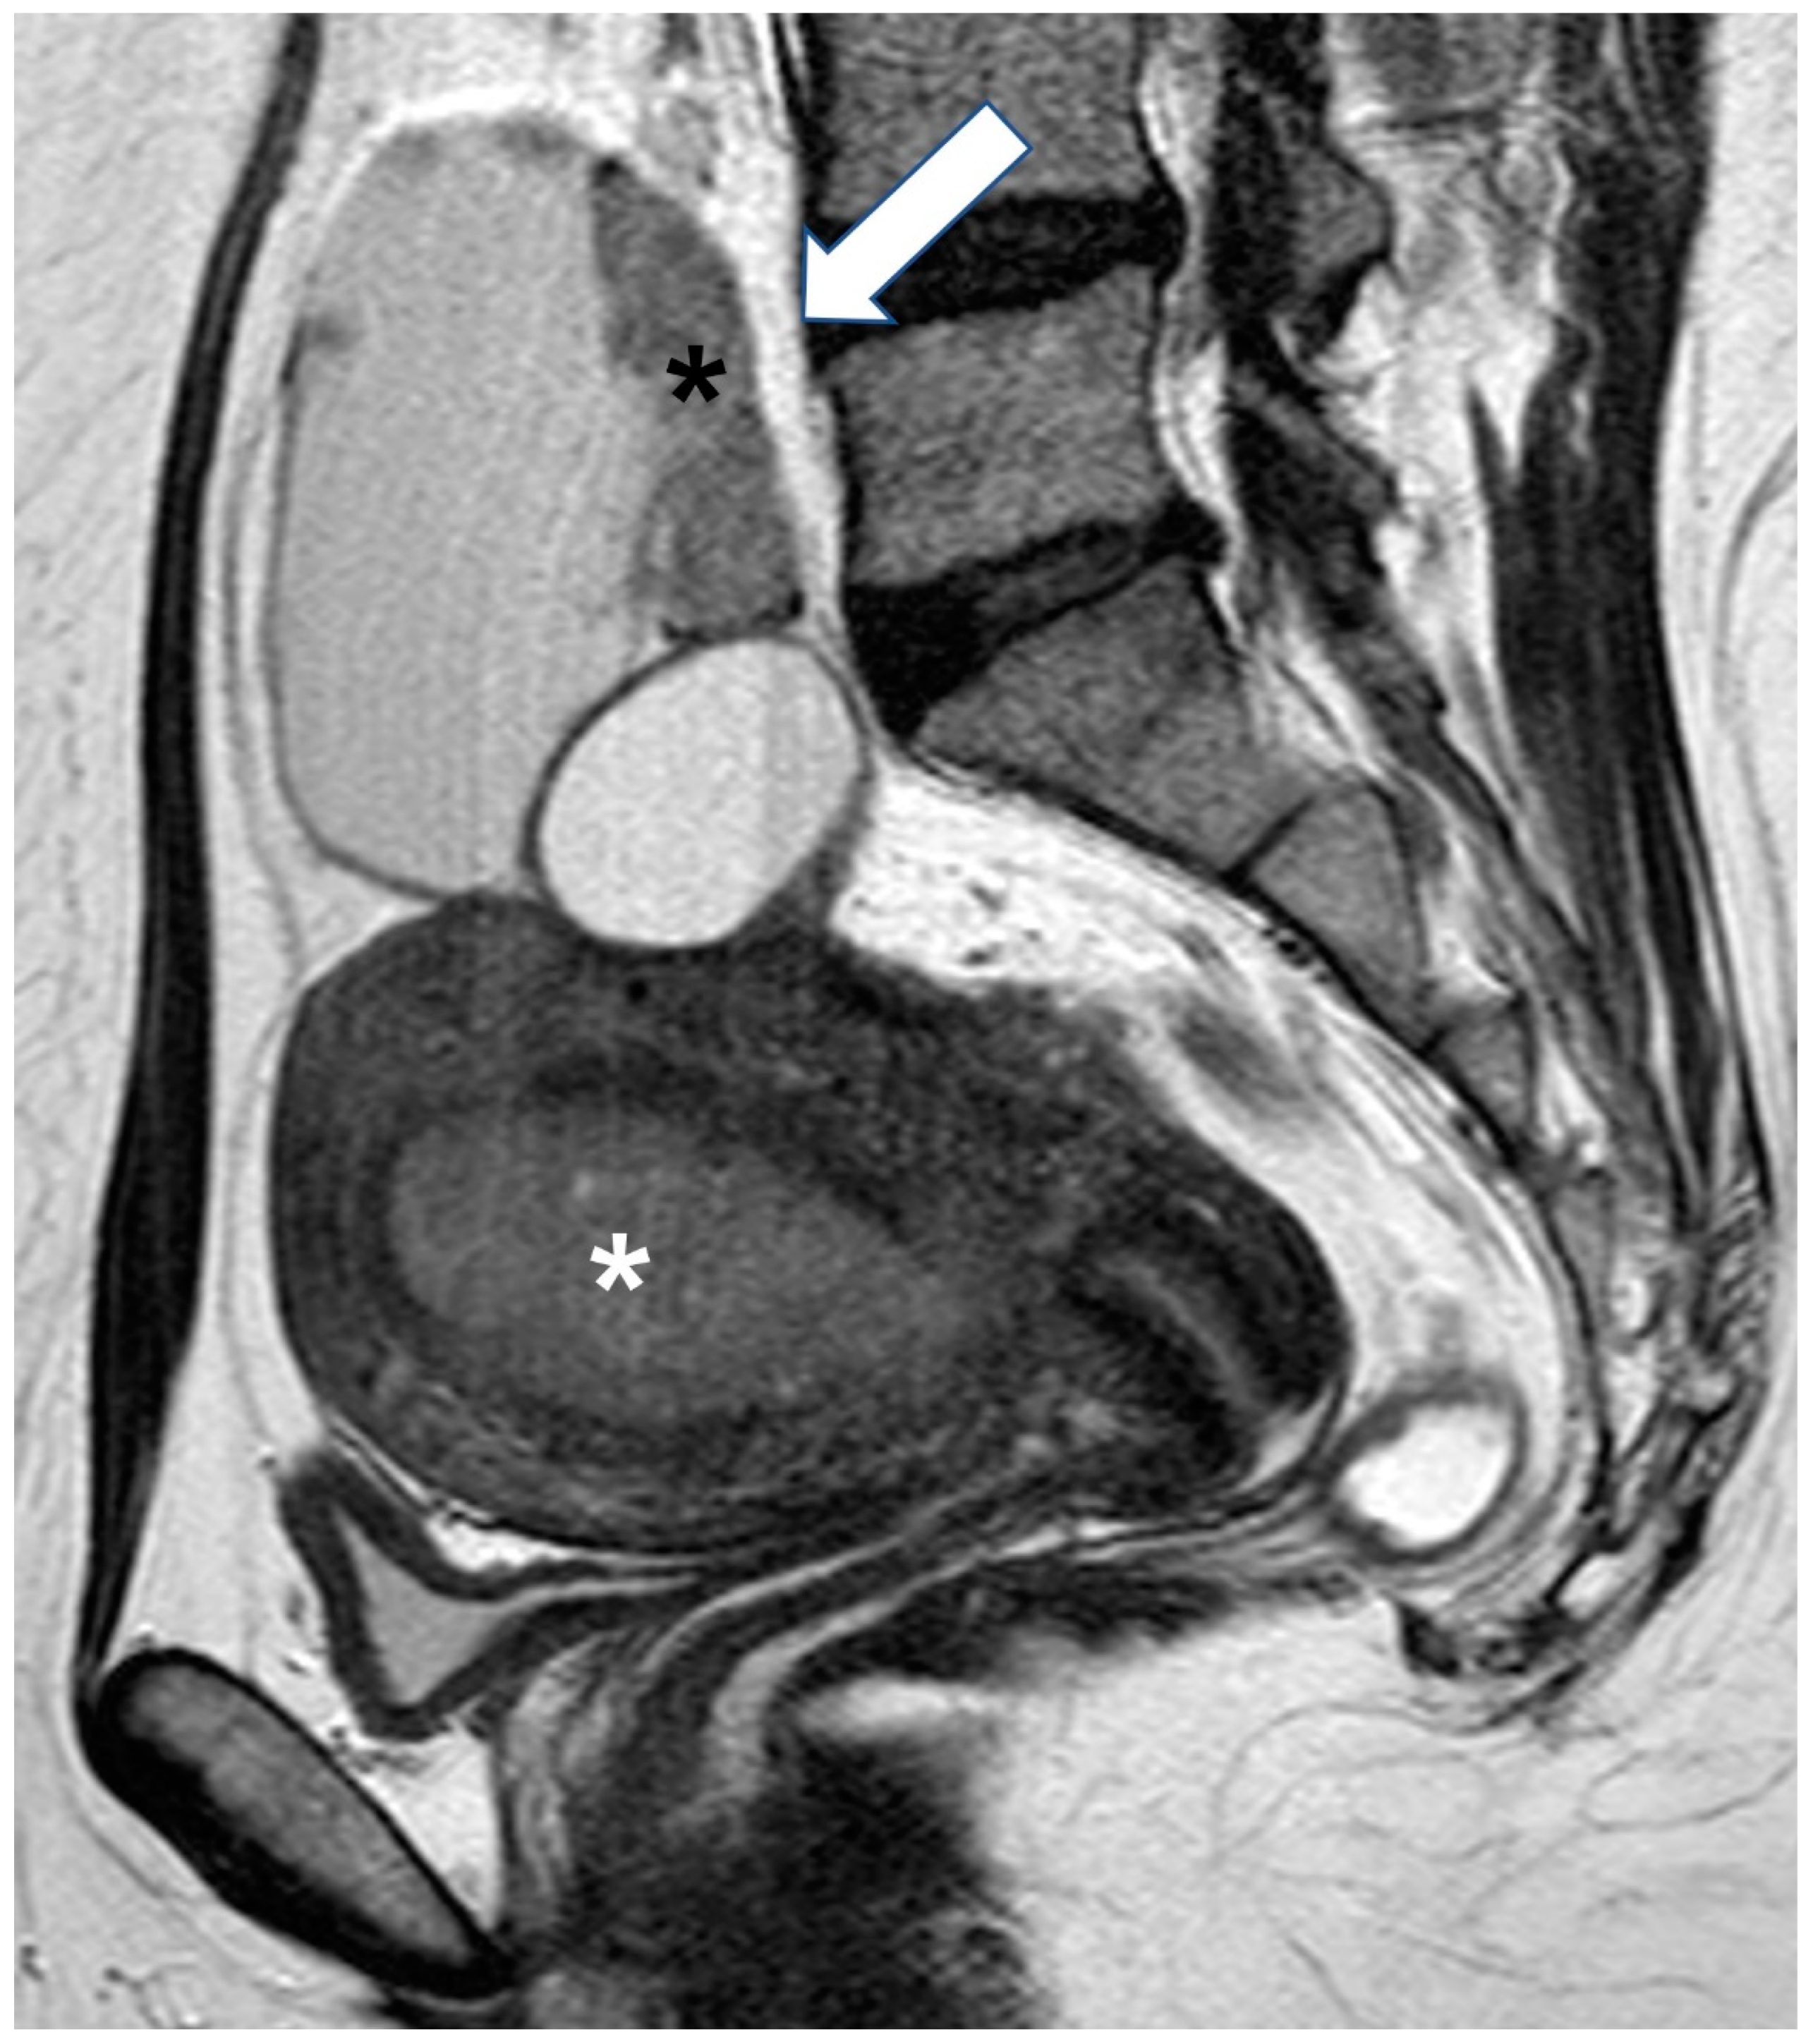

2.1.4. Endometrioid Carcinoma and Clear Cell Carcinoma

2.2. Benign Tumors That Can Mimic EOC